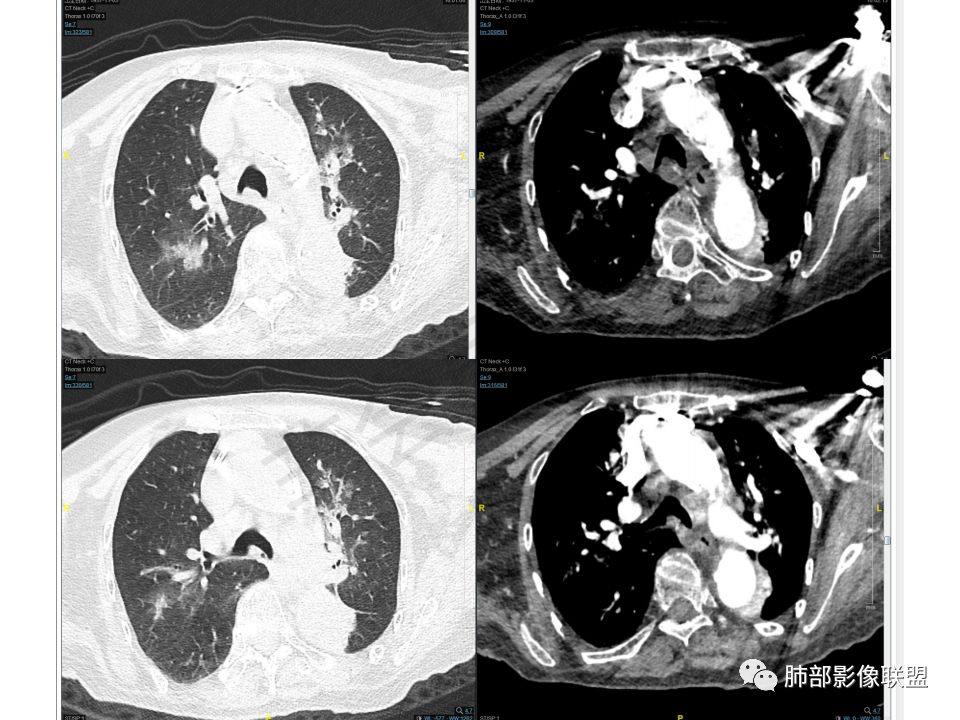

老年女性,间断咯血两年。影像:气管内带蒂结节,边缘光滑明显强化。左肺下叶背段支气管截断,远端不张。两肺散在大小不等结节及磨玻璃影,明显强化,磨玻璃影考虑合并出血可能。纵隔多发淋巴结肿大,两侧支气管受压。综合考虑:肺癌伴两肺转移。原发气管结节还是左肺下叶背段?腺样囊性癌?类癌?

主支气管上段及中下段分叉内结节,部分气管壁间隙可见,明显强化,和双肺多发结节强化差异不大,考虑转移?。

双肺多发大小不等结块,边缘光滑,随机分布,部分融合,密度不均匀,增强后可见不均匀明显强化(富血供),肺门及纵隔淋巴结肿大融合,老年女性,综合考虑转移瘤,建议查全身脏器,必要时Pet-CT, 鉴别小细胞肺癌。

老年女性,病史2年,以咯血丶贫血为主,CT:气管内带蒂肿物丶双肺多发球型团块与结节,明显强化丶程度一致,故考虑同源,富血供。纵隔7组淋巴结肿大,脂肪间隙不清。